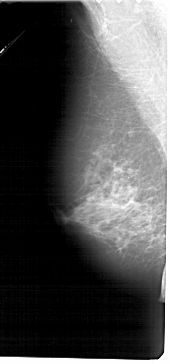

A_1277_1.LEFT_MLO

LEFT_MLO LINES 5446 PIXELS_PER_LINE 2536 BITS_PER_PIXEL 12 RESOLUTION 43.5 NON_OVERLAY